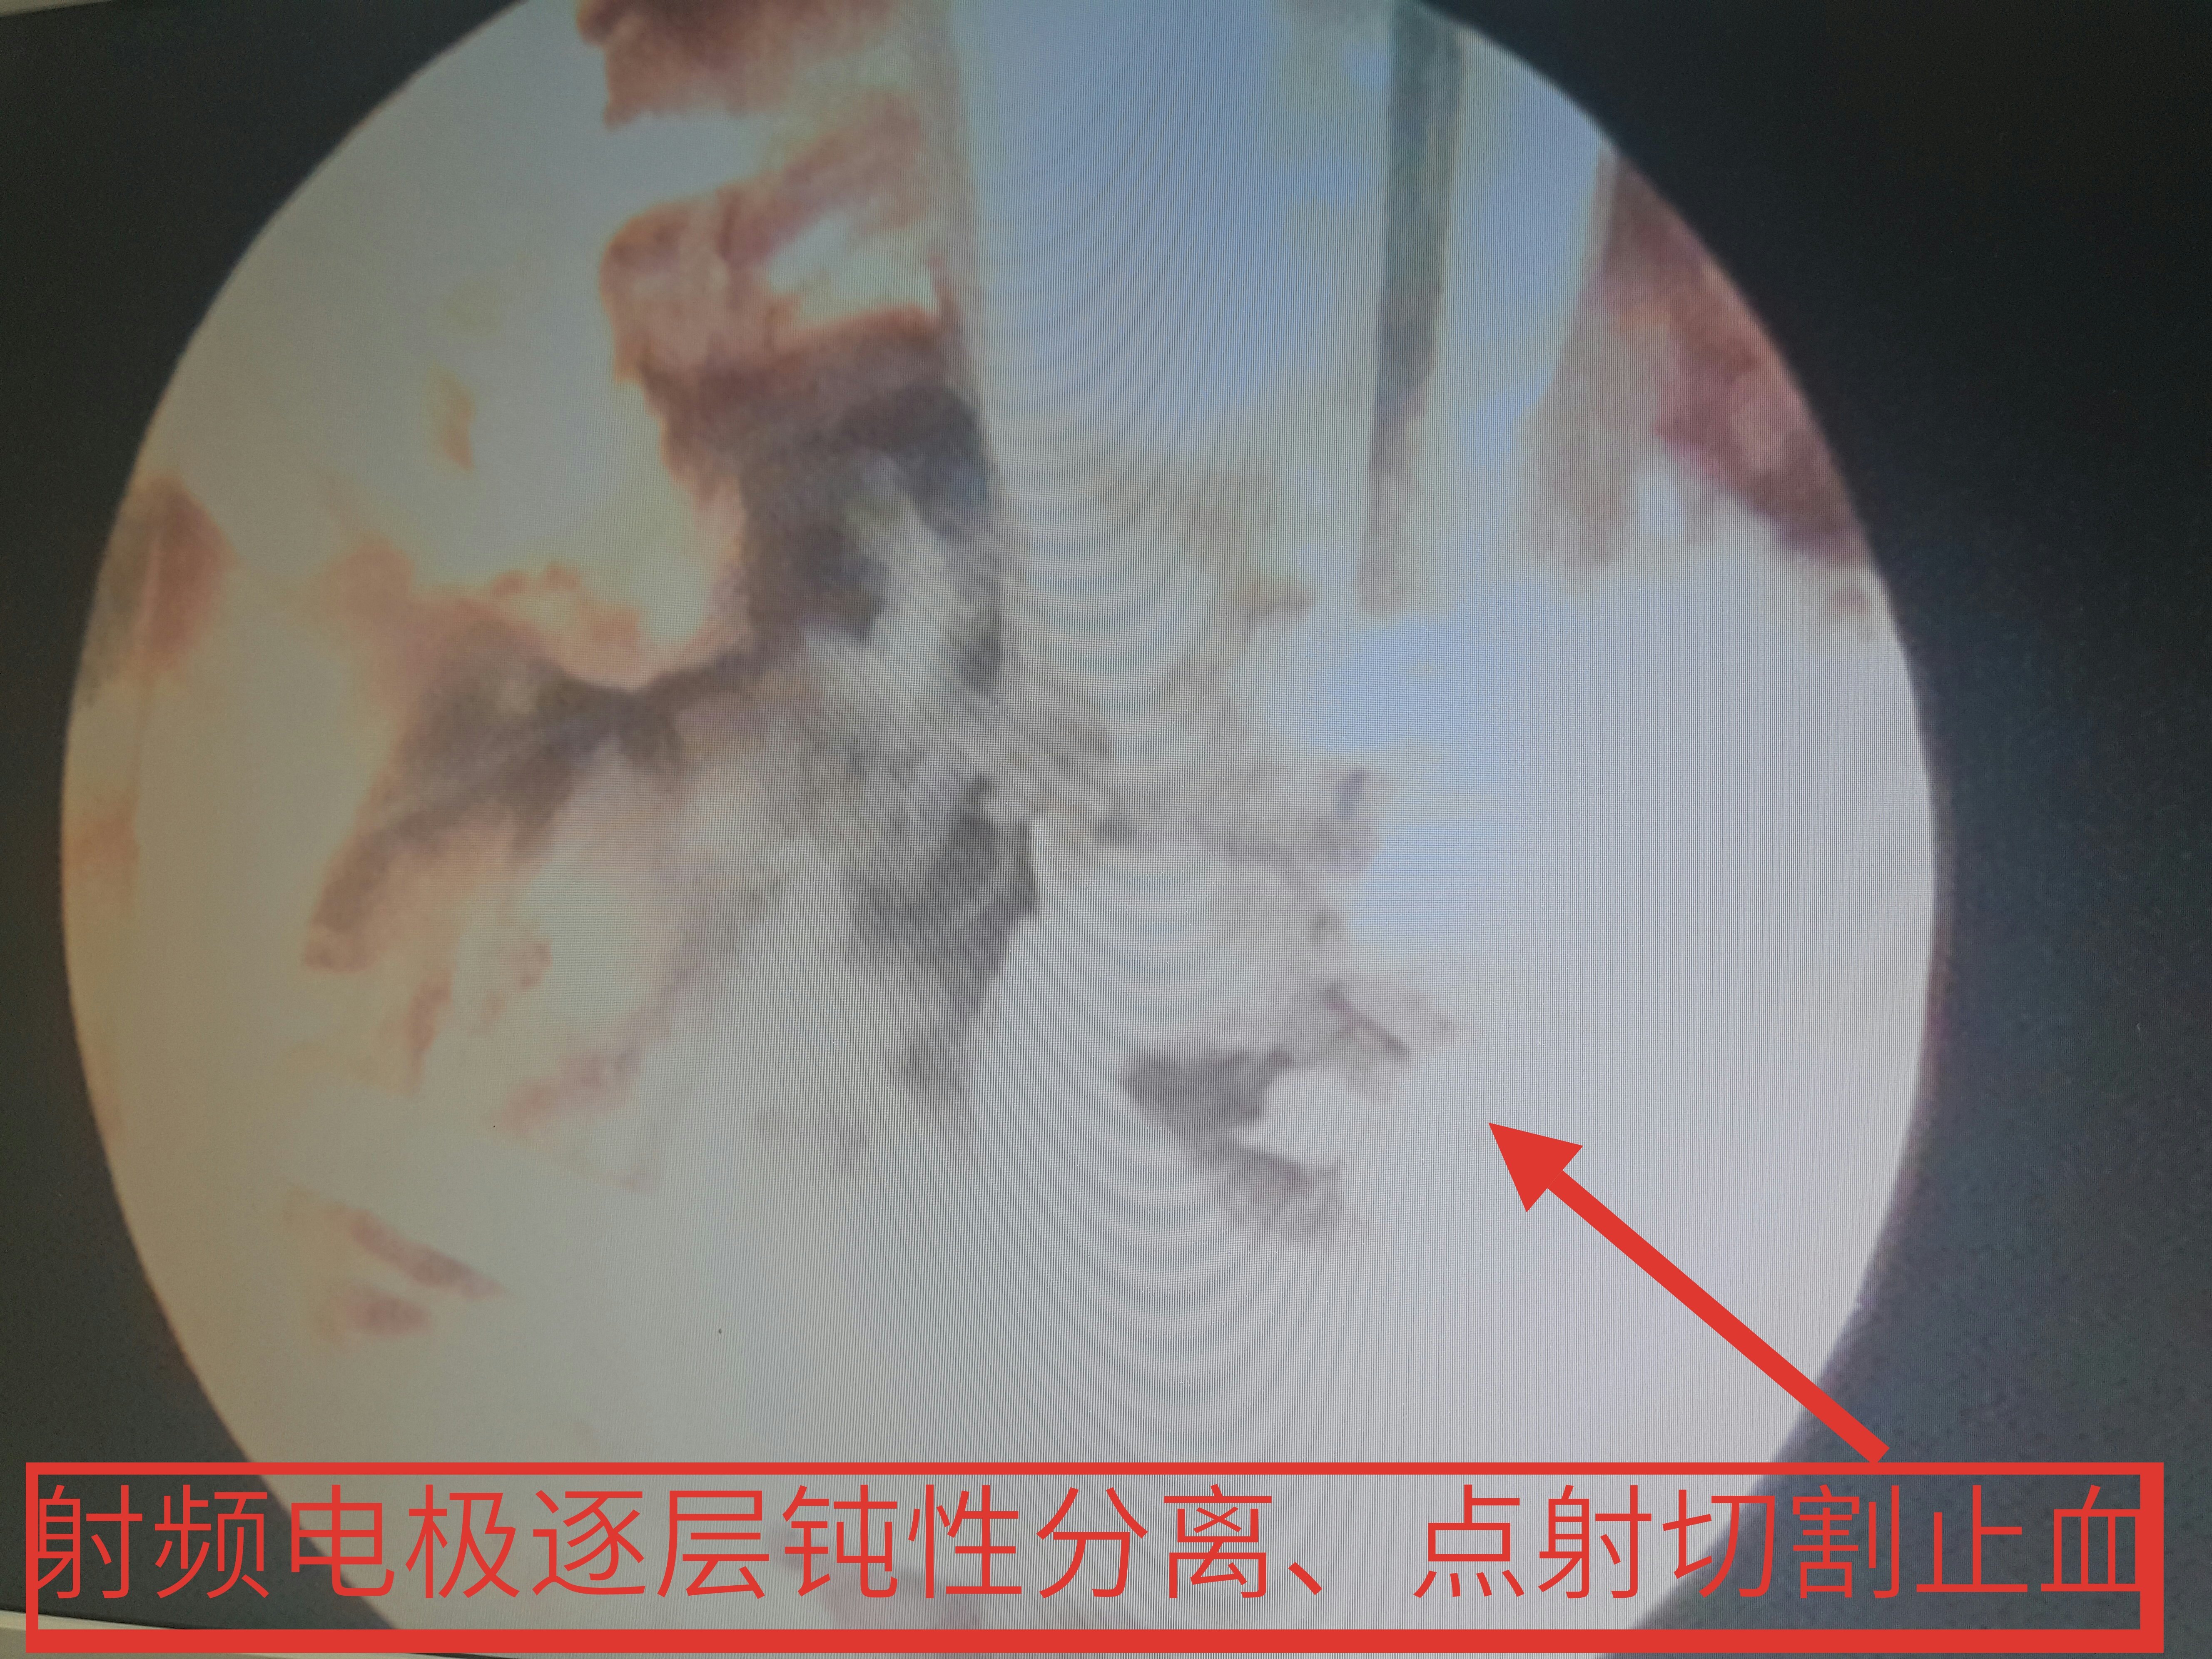

脊柱内镜翻修腰椎间盘突出症胶原酶溶核术后复

5312x3984 - 2972KB - JPEG